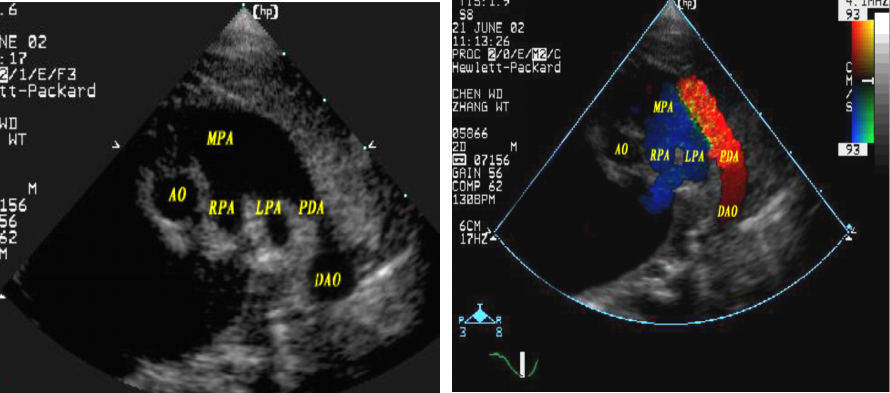

动脉导管未闭:超声心动图表现